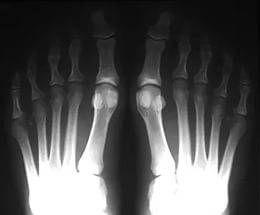

В системе предусмотрена возможность переключения негативного и позитивного изображения.

Происходит переключение негативного изображения на позитивное изображение или переключение позитивного изображения на негативное изображение.